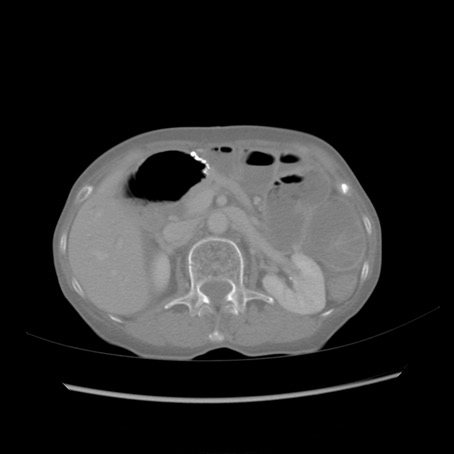

症例25(横断像)

【症例】80歳代女性

【主訴】胸のつかえ感

【現病歴】約9時間前に食後から胸のつかえた感じあり、嘔吐あり、来院。

【既往歴】胃癌(全摘)、胆摘、虫垂炎

【身体所見】心窩部に圧痛あり、反跳痛なし。

【データ】WBC 5700、CRP 0.05